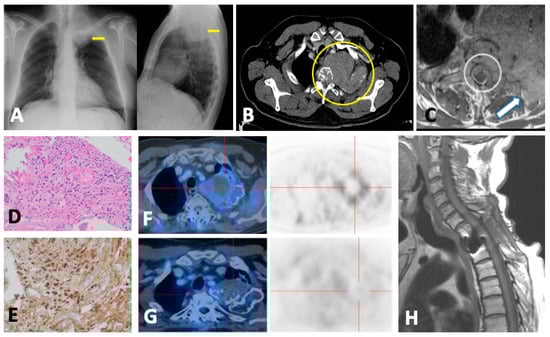

6. Plasmacytoma and Extramedullary MM